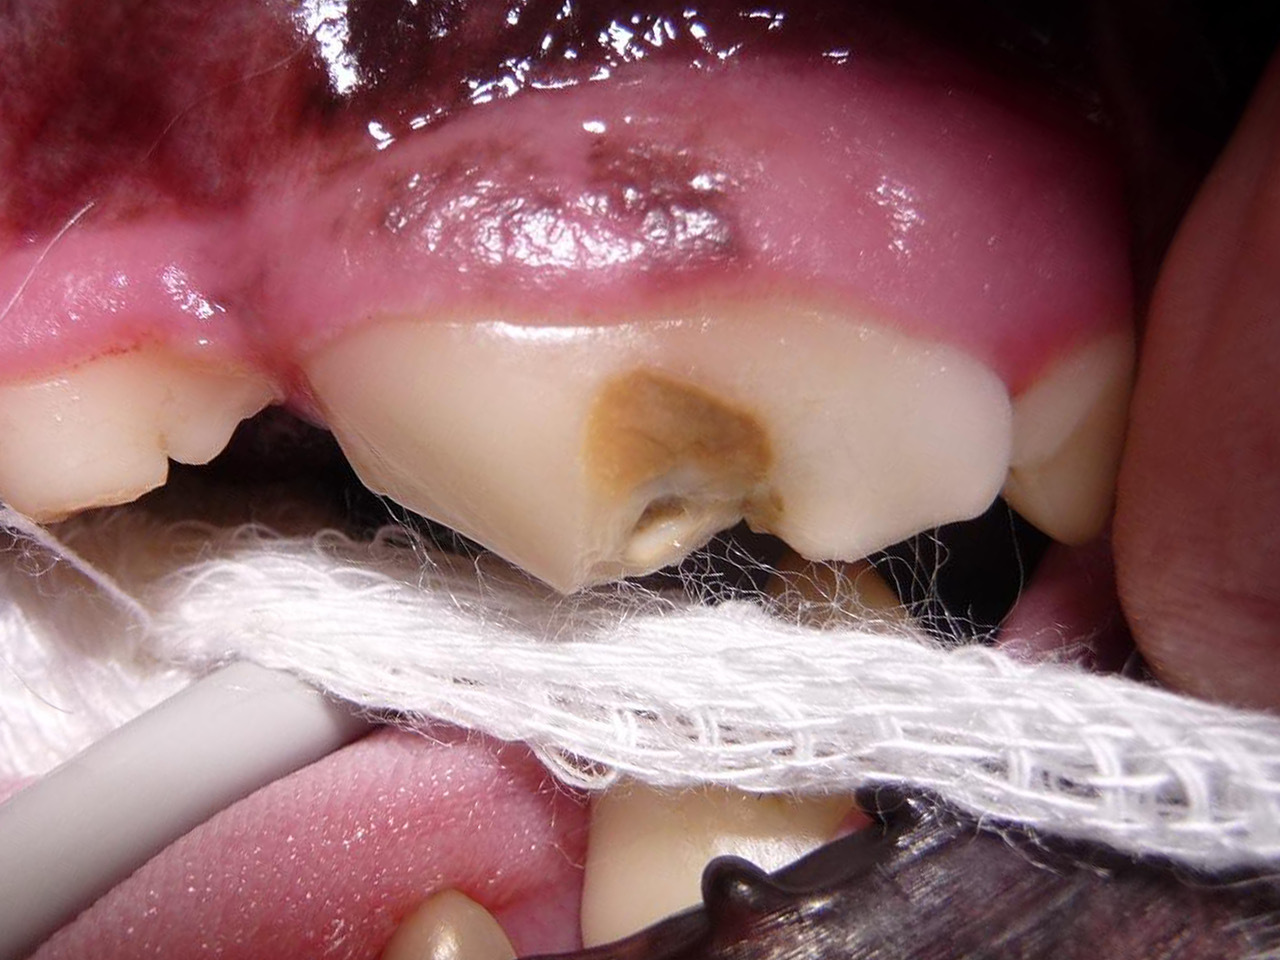

Bei Mia gibt es außer der bekannten Zahnfraktur des linken Oberkieferreißzahns (Prämolarer 4) keine Auffälligkeiten. Bei der Sondierung und Betrachtung der Bruchkante mit der Lupenbrille zeigt sich, dass noch eine ganz feine Schicht Zahnsubstanz (Dentin) Mias Wurzelkanal bedeckt. Das Dentin bietet zwar noch einen gewissen Schutz, im Gegensatz zum Zahnschmelz (der beim gesunden Zahn die äußerste Schicht der Zahnkrone bildet) hat es jedoch feine Kanälchen durch die Bakterien eindringen könnten. Im Röntgenbild zeigt sich bisher kein Hinweis für eine bestehende Infektion, und zusammen mit der Besitzerin wird entschieden, dass Mia den Zahn erstmal behalten darf, aber in sechs Monaten erneut zur Zahnröntgenkontrolle kommen muss. Da die feine Dentinschicht über dem Wurzelkanal weder vor Infektionen noch vor Umwelteinflüssen schützt, wird die Bruchkante mit dem Bohrer geglättet und der Zahn mit Kunststoff versiegelt.